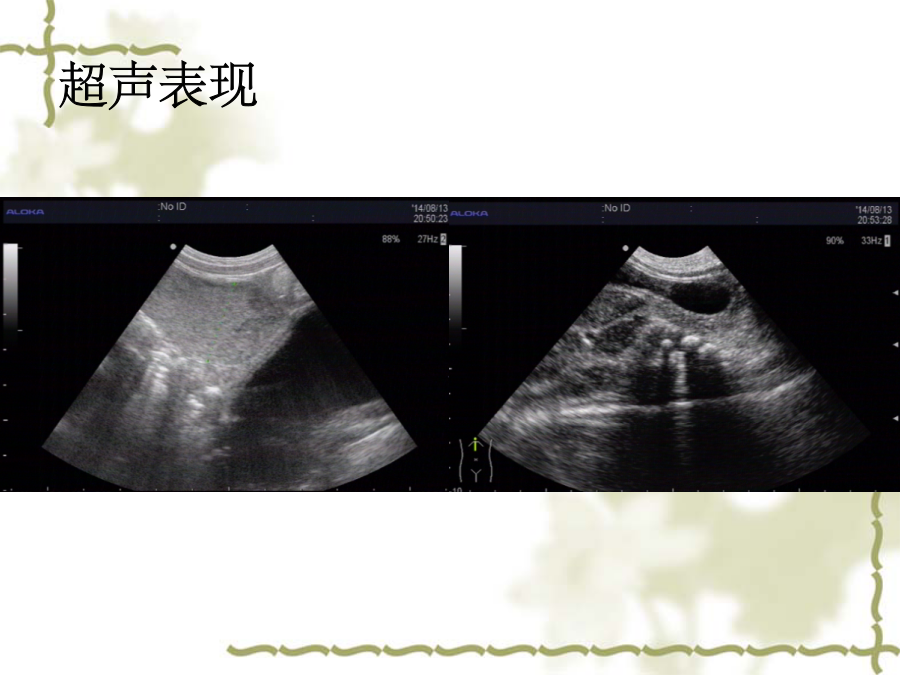

肛门闭锁的分类及超声表现患儿情况超声表现超声探查: 经肛穴处探查未探及明显肠管盲端, 经腹部探查于膀胱后方可见肠管盲端。 诊断: 肛门畸形(考虑:直肠高位闭锁) 腹部倒立位平片先天性直肠肛管畸形 最常见的消化道畸形 常伴发泌尿生殖系统及心脏神经性通畸形,约50%。 直肠肛管畸形分类(wingspread分类法1984)检查方法女性耻骨尾骨连线观察要点诊断标准(综合评价)谢谢感谢亲观看此幻灯片,此课件部分内容来源于网络, 如有侵权请及时联系我们删除,谢谢配合!